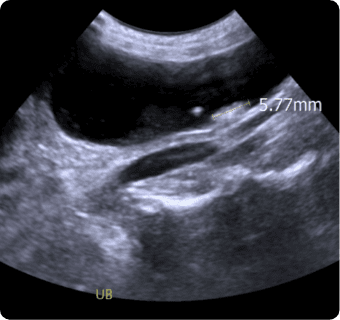

일산시티동물의료센터는 지멘스에서 개발한 고성능 프리미엄 초음파 장비인

Siemens Sequoia를 활용하여 심장, 복부 장기, 림프절 등의 구조물을 선명하게 구현하고,

미세한 해부학적 구조까지 정밀하게 확인할 수 있습니다.

또한 급성 췌장염, 급성 신부전, 자궁축농증, 방광염, 요로결석, 소화기 이물,

비장종양 등의 질환을 진단하고, 환자의 상태를 평가하는 데에도 활용됩니다.